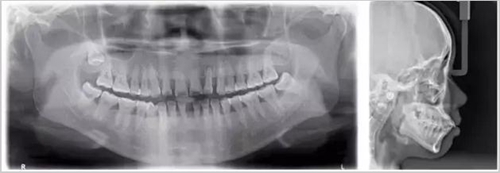

暗的部位說明齲齒已經(jīng)非常嚴(yán)重了!

上面這個(gè)是接近牙髓了!